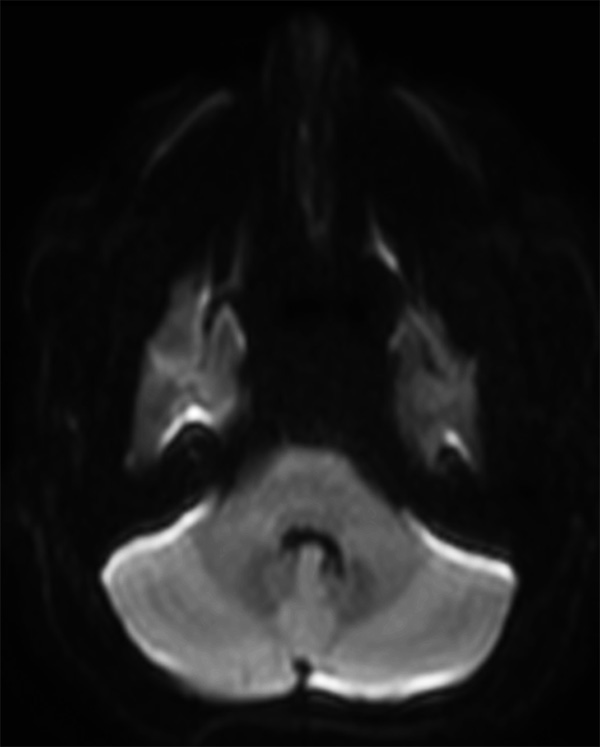

Comprehensive Brain imaging at 3.0T

• Clinical Application